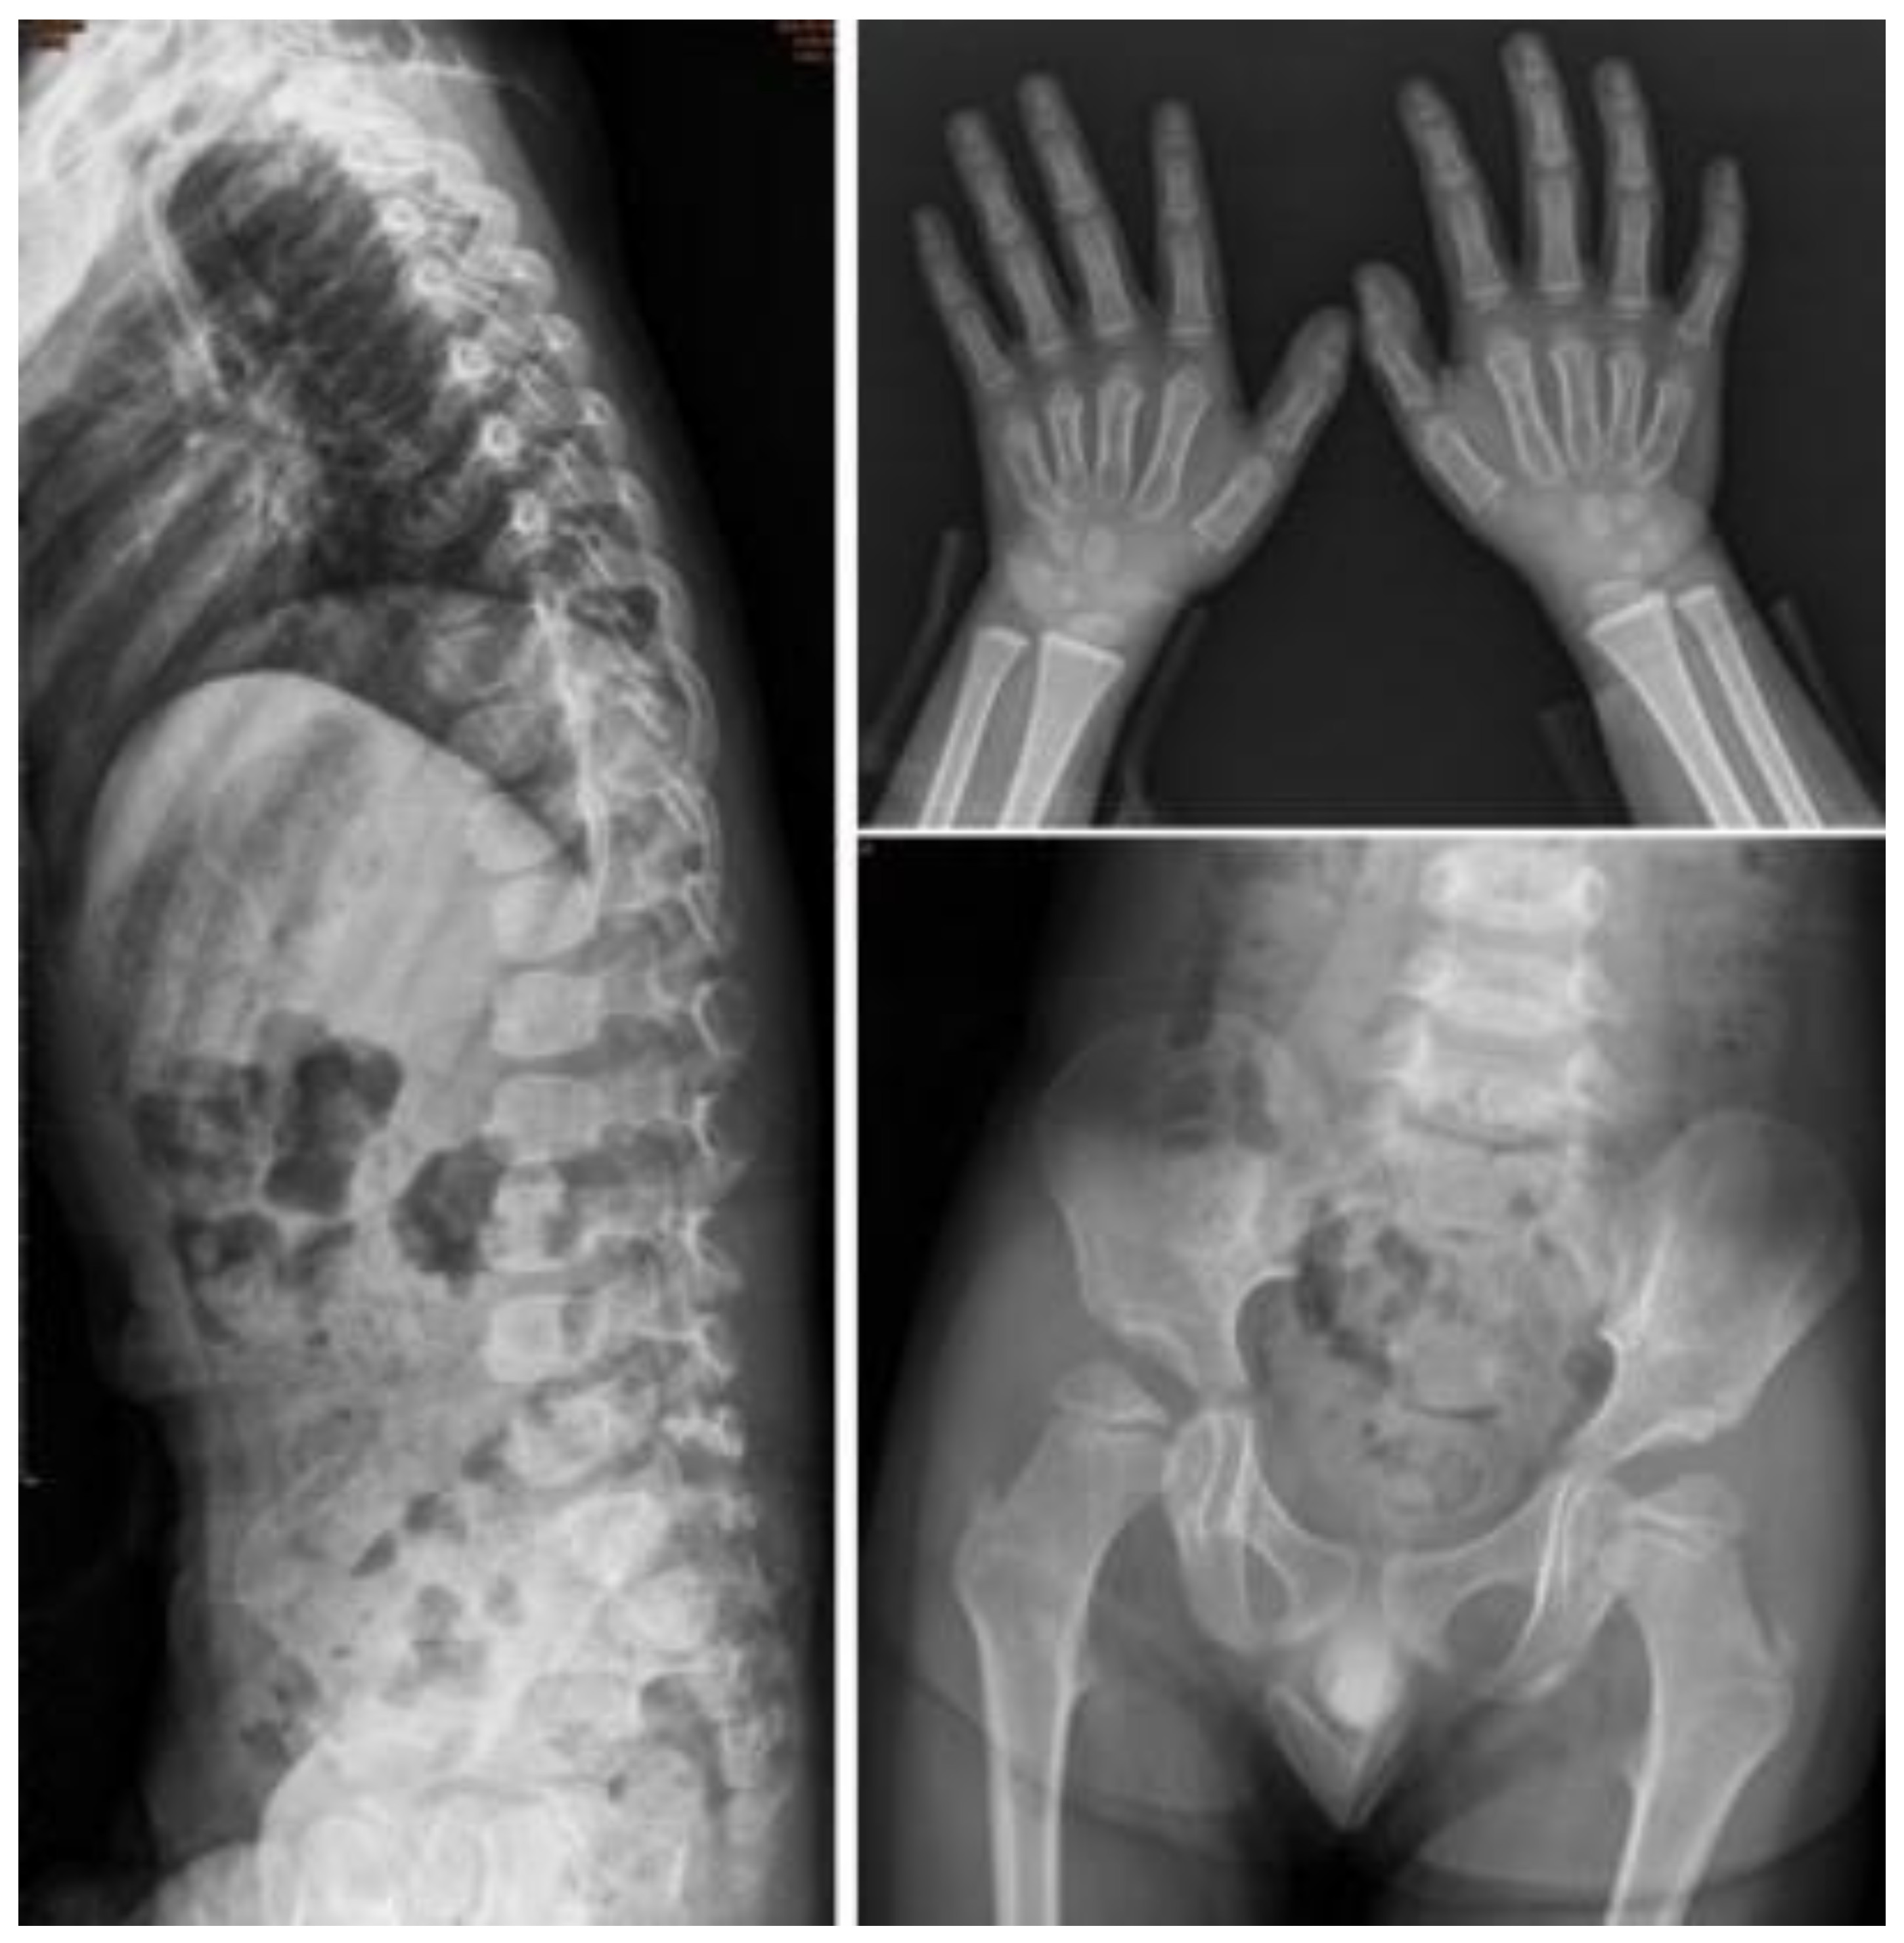

| I-6 | M | c.1007–1666_c.1180 + 2113 delinsTT | 0.9 | 0.4 | Baseline | 0.1 | 0.99 | 177.96 | 30.77 | 203.35 | 0.31 | Normal | Normal | Normal | ASD II | Normal |

| Follow-up | 2.8 | 110.92 | 8.9 | 0.1 | 20.64 | 7.05 | Persistent proximal pointed metacarpal and bullet-shaped phalanges of both hands. | Anterior beaking of lower thoracic to lumbar vertebrae. Relative enlargement of sternal end of bilateral clavicles. | Shallow bilateral acetabuli and coxa valga of both femurs. | ASD II, MR, AR | Mild splenomegaly | |||||